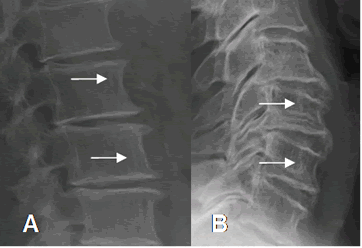

En la columna hay prominencia de las trabéculas verticales, por reabsorción de las horizontales. (Fig 36).

Fig 36. Osteoporosis.

A: Rx lateral de columna lumbar y B: Rx lateral de columna cervical.

Disminución de la densidad ósea, con prominencia de las trabéculas verticales.